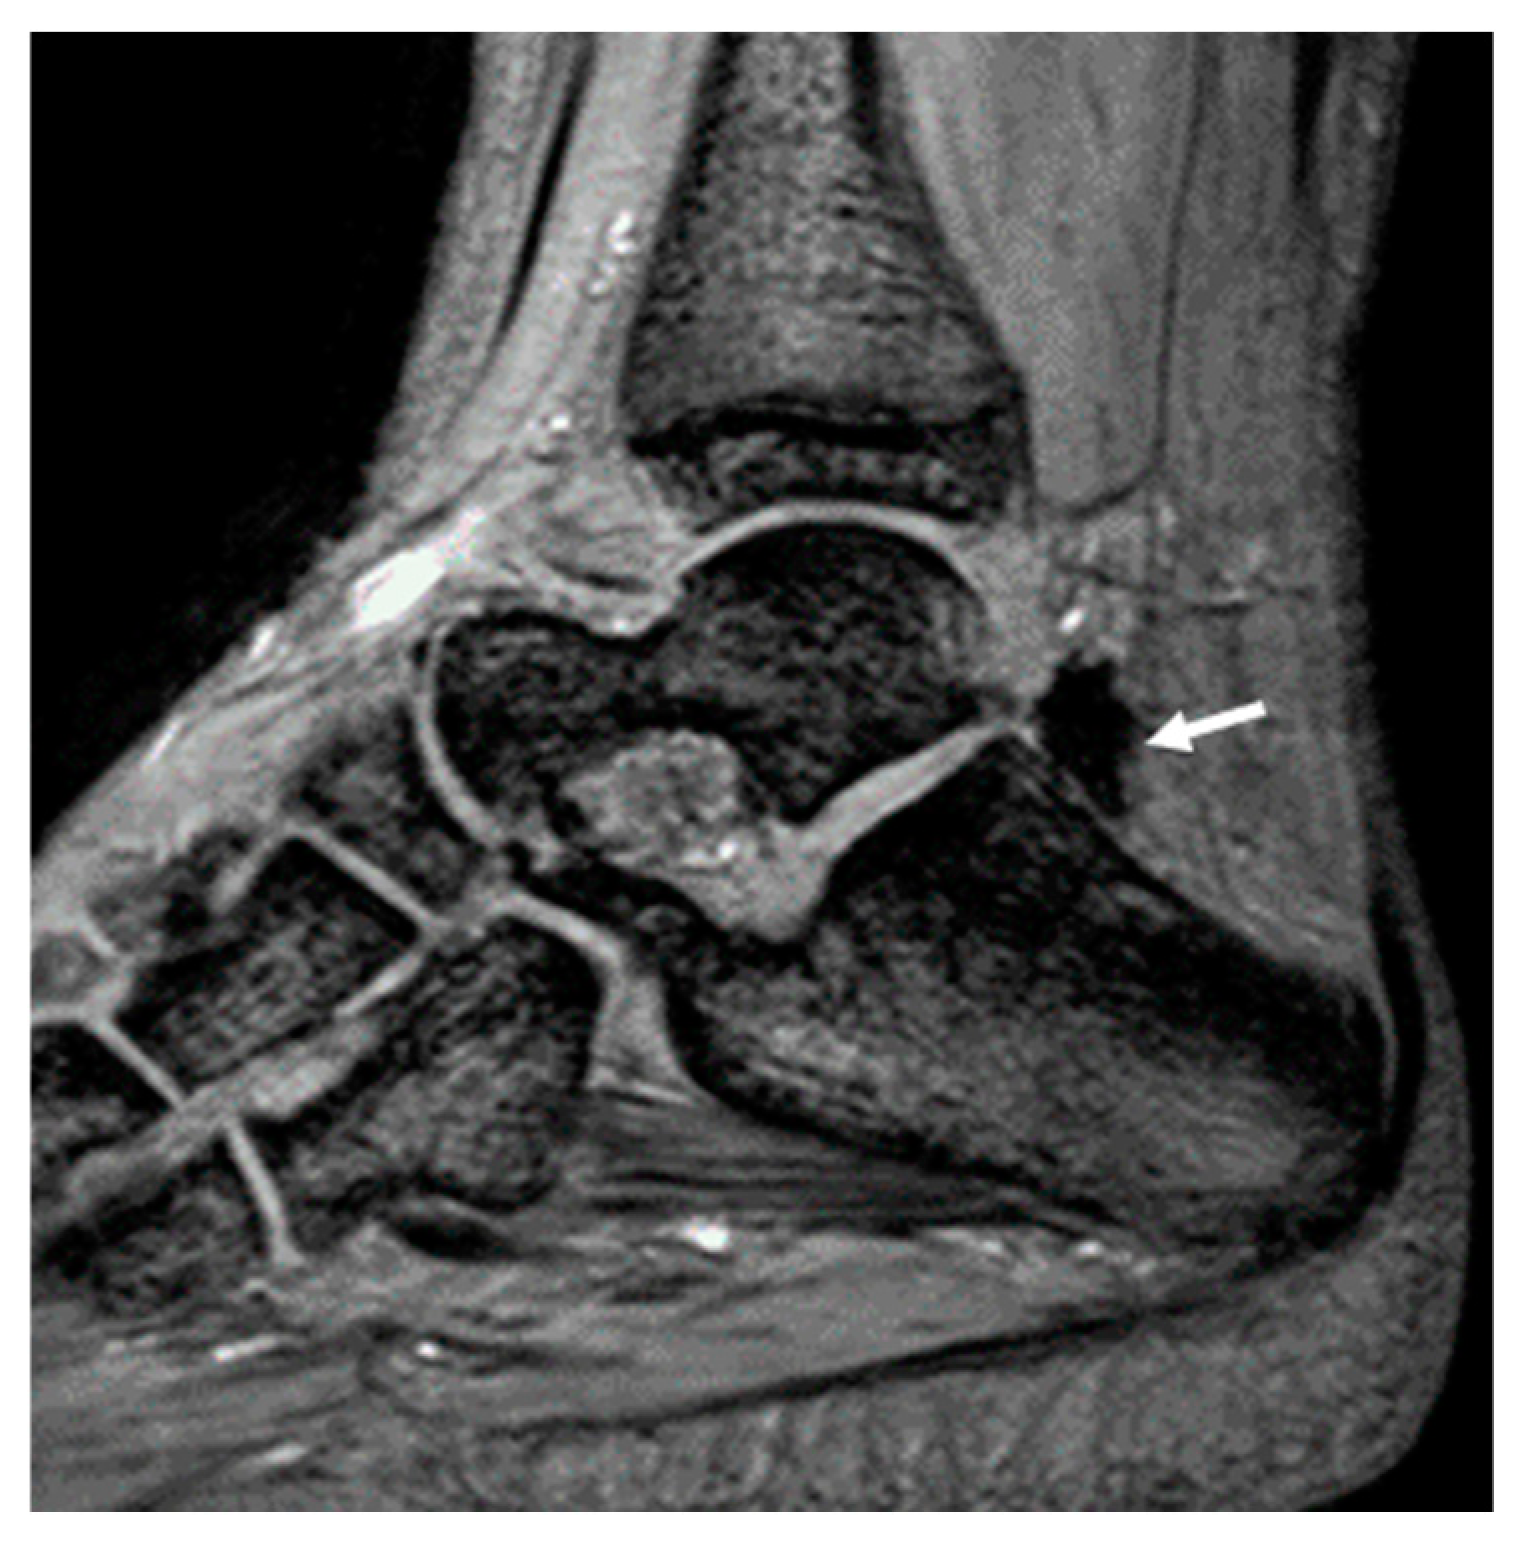

3.2. The Association of Joint Hemosiderin Deposition with Synovial Thickening, Effusion, and Osteochondral Changes (OCC)

3.3. Association of Joint Hemosiderin Deposition with the Number and Chronicity of Joint Bleeds and Clinical Score